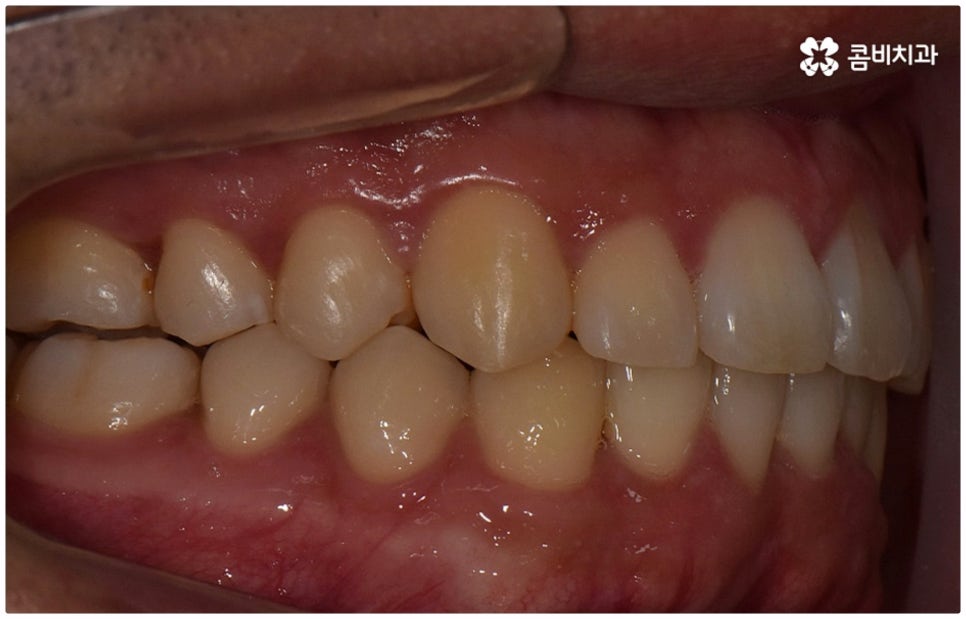

물론 교정 치료에 적기가 정해져 있는 것은 아니기 때문에 성인 이후 중장년 환자분들이라도 교정 치료가 불가능하지는 않으며 상황에 따라 비수술적인 방법으로도 얼마든지 불편함을 줄일 수 있는 경우가 있으니 정확하게 진단한 후 각자에게 맞는 교정 계획을 세워 무리하지 않게 치료를 진행하시길 바라고 있어요. 특히 턱관절과 관련된 부분을 개선하기 위해서는 양악 수술 밖에 방법이 없는 것이 아닌가 생각하셨던 분들이라면 먼저 치과에 내원하셔서 검진과 상담부터 진행해 보시면 마음의 부담을 덜 수 있어 좋을 거예요. 부정교합 3급 치열 (절단교합과 일부 반대교합이 병행되어 있음) 을 가지고 있는 성인분도 교정 치료를 통해 훨씬 자연스럽게 개선이 가능할 수 있으며, 관련 기술 개발 및 미니스크류 등 여러 장치의 발전을 통해 예전에는 적용이 어려웠던 케이스들도 이제는 교정 치료의 도움을 받을 수 있습니다.

위 사진은 이해를 돕기 위한 이미지이며, 환자의 동의하에 진행되었습니다.

전체 치료 기간은 약 18개월이 소요되었으며,

개인에 따라 출혈 및 부작용이 발생할 수 있고,

환자마다 치료 결과 및 기간이 상이할 수 있으므로,

정확한 치료 기간 및 치료 계획은

치과에서 상담을 받아보시길 권장 드립니다.